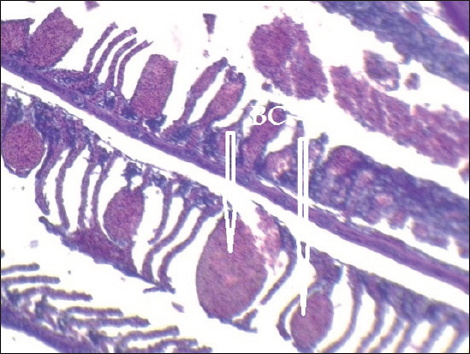

Histopathological findings of gill section showed telangictatisis and epithelial lifting in secondary lamellae (Fig. 7) with hemorrhage and blood congestion (Fig. 8), also, the result showed the central venous dilation with blood congestion and epithelium hyperplasia with complete fusion of the secondary lamellae (Figs. 9 and 10) and edema in the filamentary epithelium (Fig. 11) in addition to mononuclear cells infiltration (Figs. 12 and 13).

Fig. 8. Histopathological sections of gill of C. carpio showing severe telangiectasia in secondary lamellae with hemorrhage and blood congestion (BC) (H&E X10).